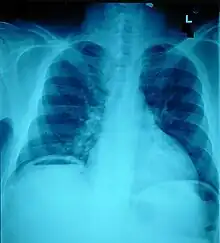

Abdominal trauma resulting in a right kidney contusion (open arrow) and blood surrounding the kidney (closed arrow) as seen on CT | |